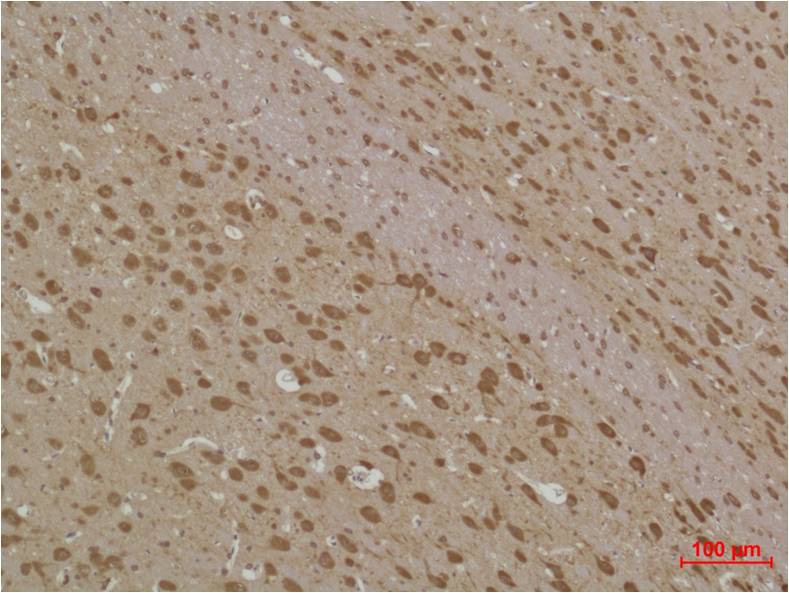

IHC 1/50-1/100 Human,Mouse,Rat

4. **文献名称**: *Autophagy Marker LC3B Correlates with Glioma Prognosis*

**作者**: Huang, R. et al.

**摘要**: 通过免疫组化分析LC3B在胶质瘤组织中的表达水平,发现其与患者生存率显著相关,提示LC3B抗体在肿瘤自噬活性评估及预后预测中的潜在临床价值。

LC3B antibodies are essential tools for detecting and quantifying autophagy in research. They are employed in techniques like Western blotting, immunofluorescence, and immunohistochemistry to distinguish between LC3B-I and LC3B-II, with the LC3B-II/I ratio or puncta formation indicating autophagic flux. Specificity for LC3B isoforms (e.g., distinguishing LC3B from other LC3/Atg8 family members) is critical for accurate interpretation. These antibodies are applied in studying autophagy-related diseases, including cancer, neurodegenerative disorders (e.g., Alzheimer’s), and infections, where dysregulated autophagy contributes to pathogenesis. However, variability in antibody performance across experimental conditions and species necessitates careful validation. LC3B antibodies have advanced our understanding of autophagy mechanisms and their therapeutic targeting.